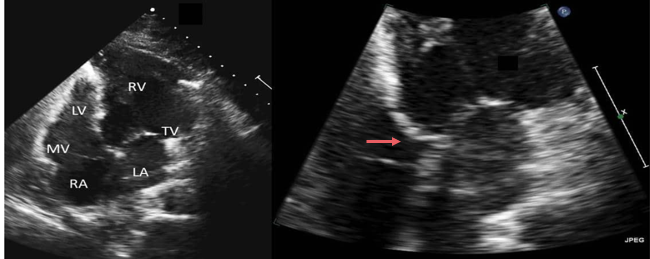

Pre op findings of CC-TGA

Septal insertion of left sided AV valve is more apically displaced than right sided valve in AP4

Notation of coarse trabeculation and moderator band in left sided ventricle (RV)

On axis PLAX not possible due to transposed and parallel great arteries

Usually has “friends” so look out for VSD, Pulmonary outflow tract obstruction, Ebstein’s anomaly, and conduction defects

RV dilation and systolic failure

Potential for large amount of TR

What are these images of?

CC-TGA

LV and RV swapped

TV and MV swapped